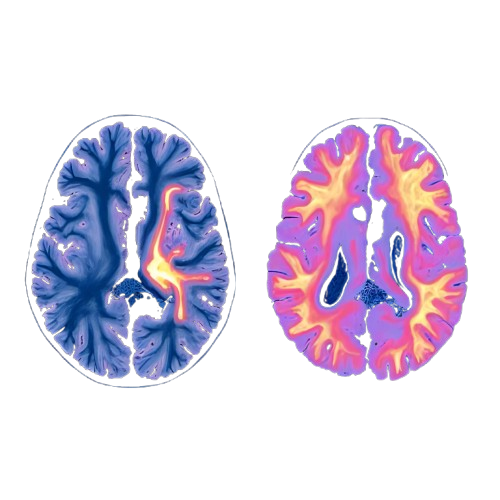

Transcranial Magnetic Stimulation (TMS) is a non-invasive procedure that uses magnetic fields to stimulate changes in the brain, resulting in symptom relief for those suffering from Major Depression.